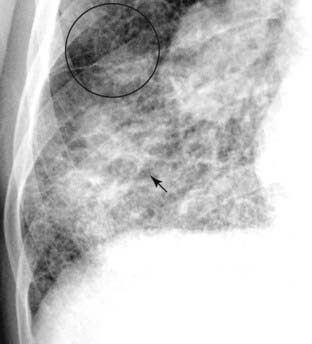

Figure 3-10 The edge of the lesion.

Notice how a portion of this disease appears confluent, like airspace disease (solid black arrow). Always look at the peripheral margins of parenchymal lung disease to best determine the nature of the “packets” of abnormality and to help in differentiating airspace disease from interstitial disease. At the periphery of this disease (black circle), this is more clearly seen to be reticular interstitial disease.